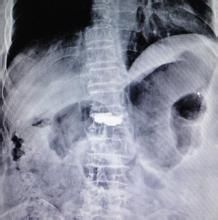

針對老年骨質疏鬆新鮮骨折,可在X線CT引導下配合體位復位,並在損傷椎體骨折間隙注入骨水泥,或先注入氣囊,擴張成形後再注入骨水泥,使被壓縮的椎體膨脹成形,加固傷椎、避免椎體進一步塌陷,隨著傷椎穩定,患者疼痛會緩解消除。